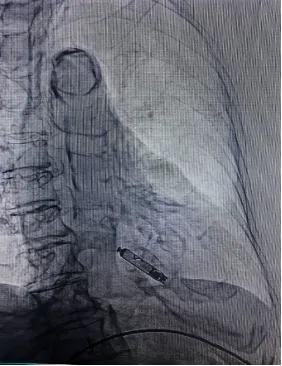

术后起搏器影像

术后程控参数良好,电池预估能用19.9年